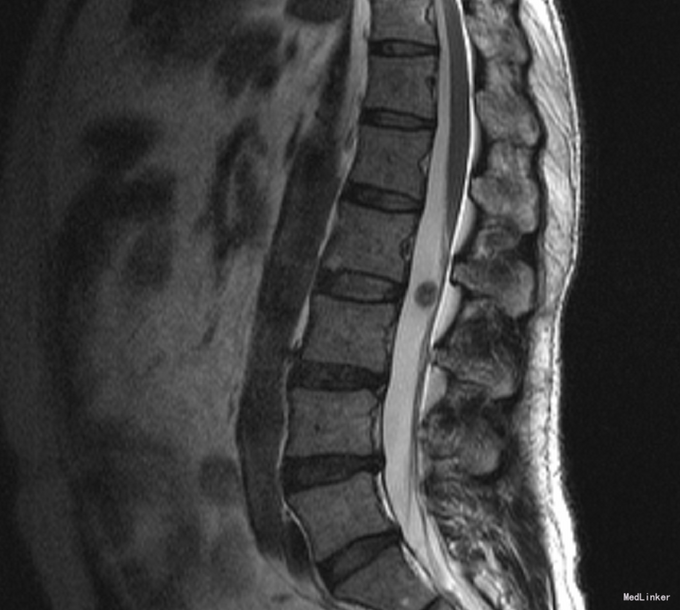

患者,男,54岁,因“ 腰背部疼痛不适5余年,加重1年”入院。

腰椎MR示:1.L2/3水平椎管内结节,脊膜瘤考虑2.腰椎退行性变,L4\5,L5/S1椎间盘突出。

诊断: L2/3神经鞘瘤?脊膜瘤?全麻下行“腰椎肿瘤切除术”,术程顺利,术中冰冻示:(椎管肿瘤 腰2-3)神经鞘瘤。